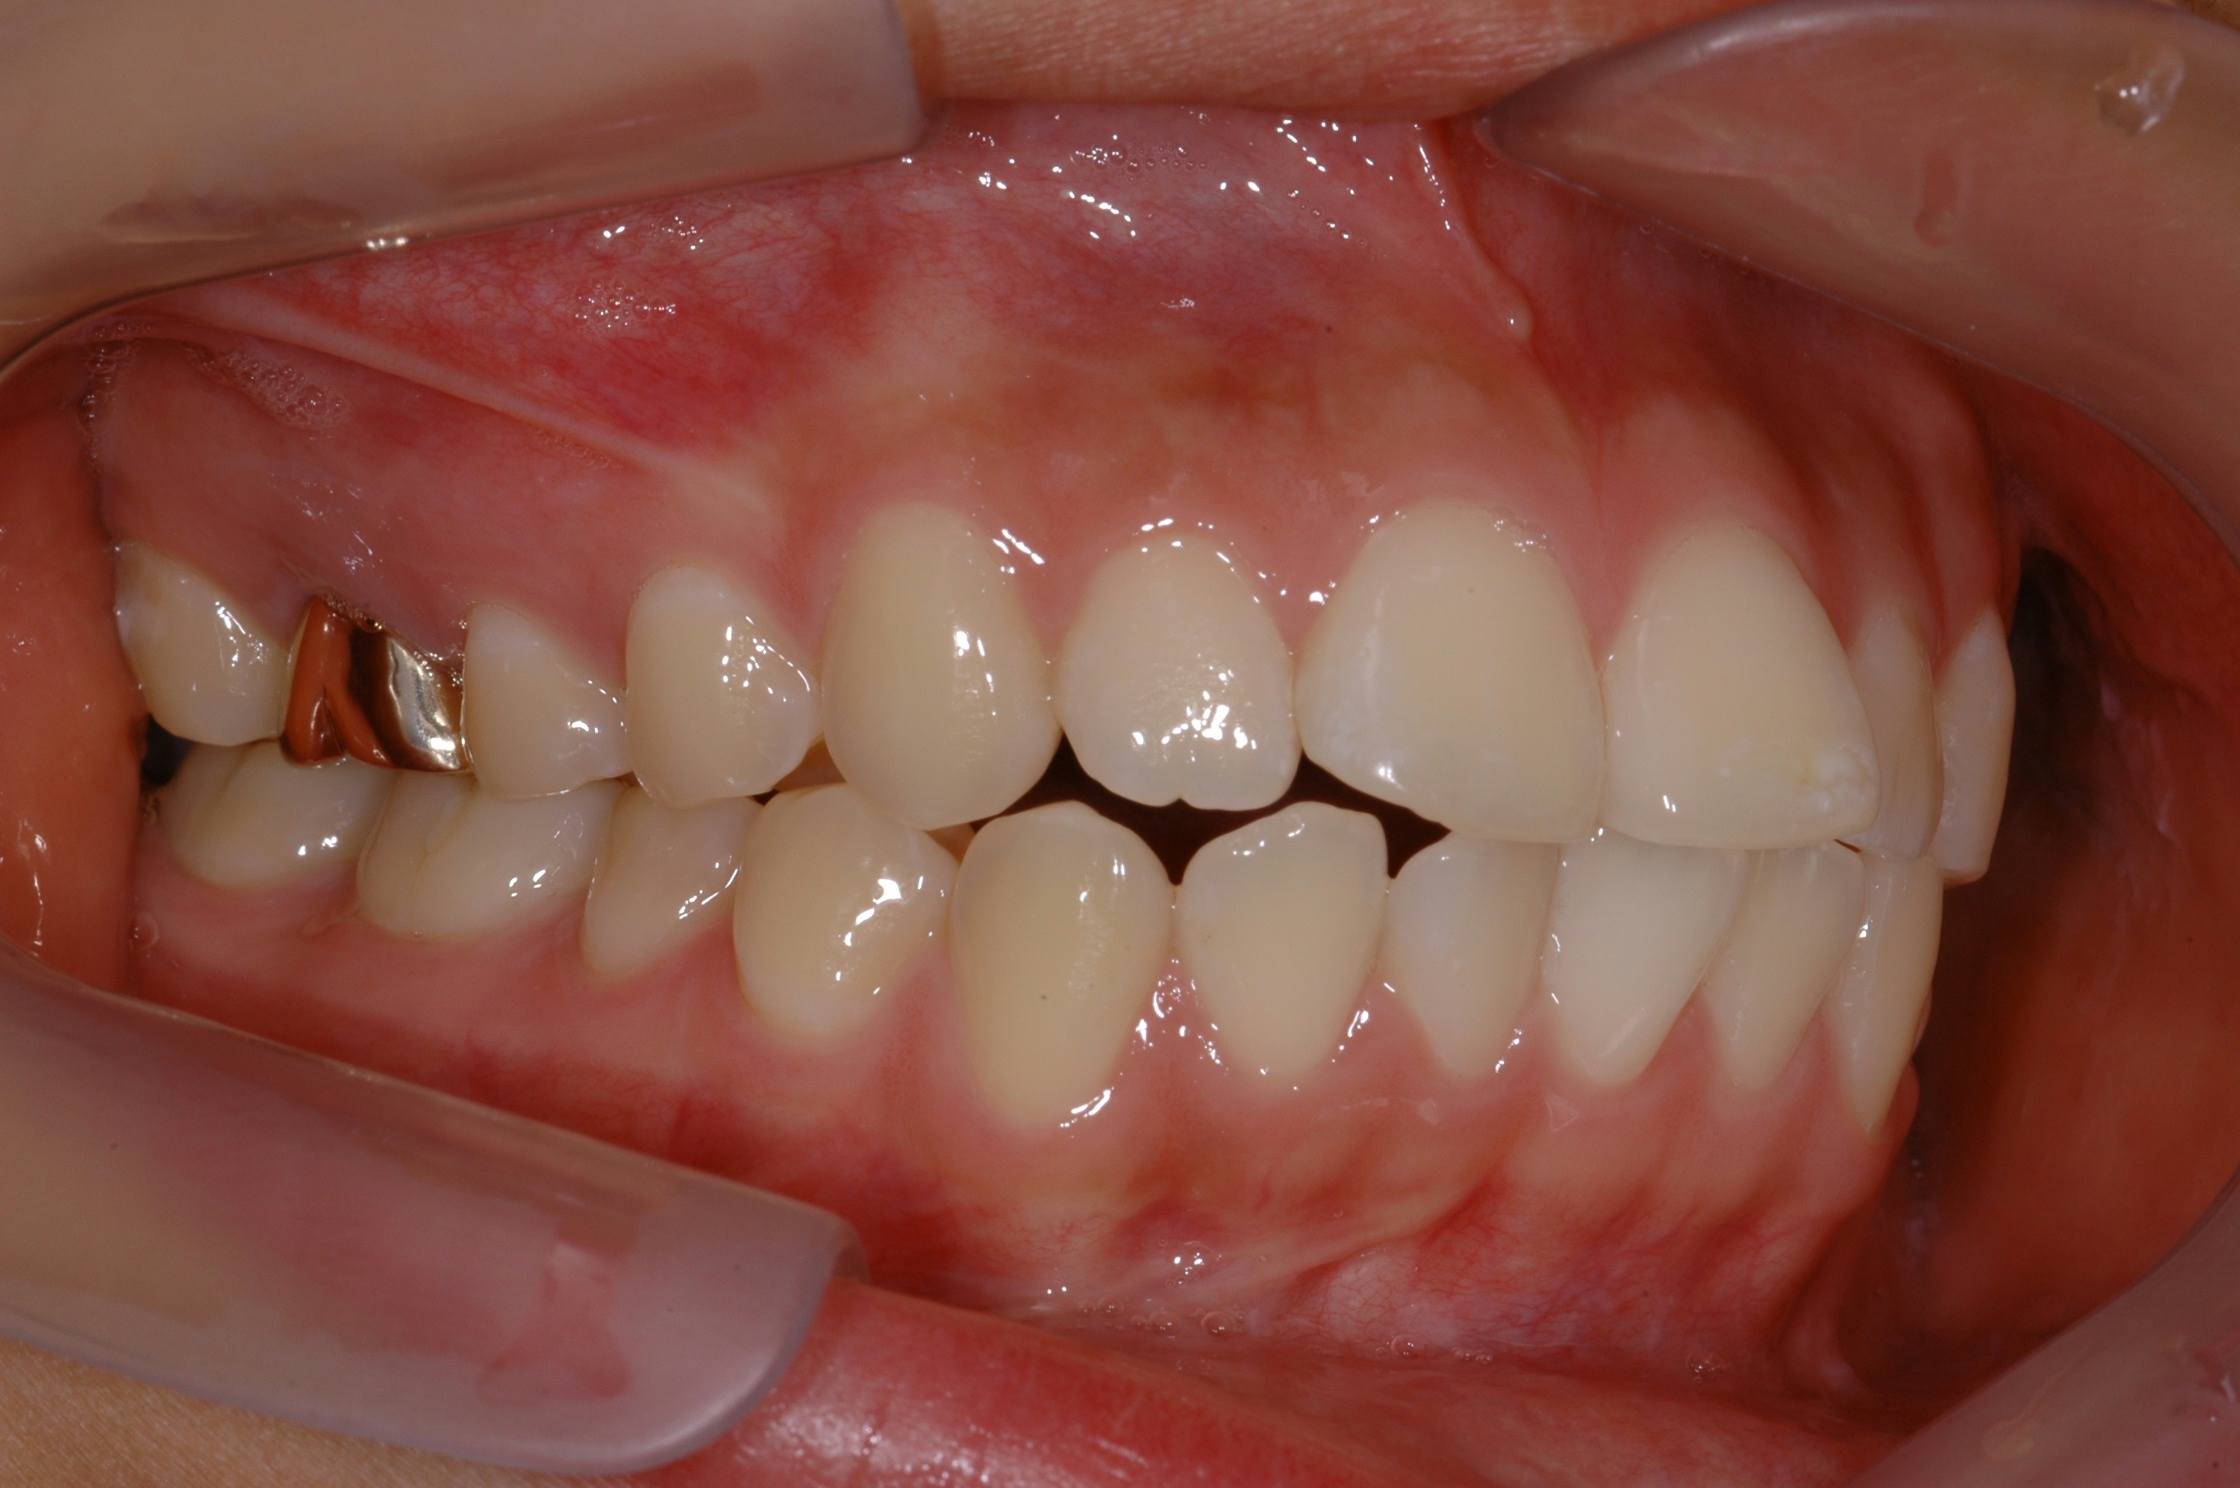

치료 후 사진입니다.